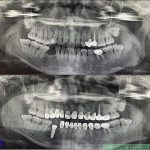

Bác cựu chiến binh U80 đã mất răng toàn bộ 2 hàm được hơn 20 năm và không đeo hàm tháo lắp trong suốt thời gian đấy khiến xương hàm teo lép, toàn bộ thời gian chỉ ăn đồ mềm và thường xuyên nuốt chửng vì không có răng để nhai. Bác đã đi khám […]